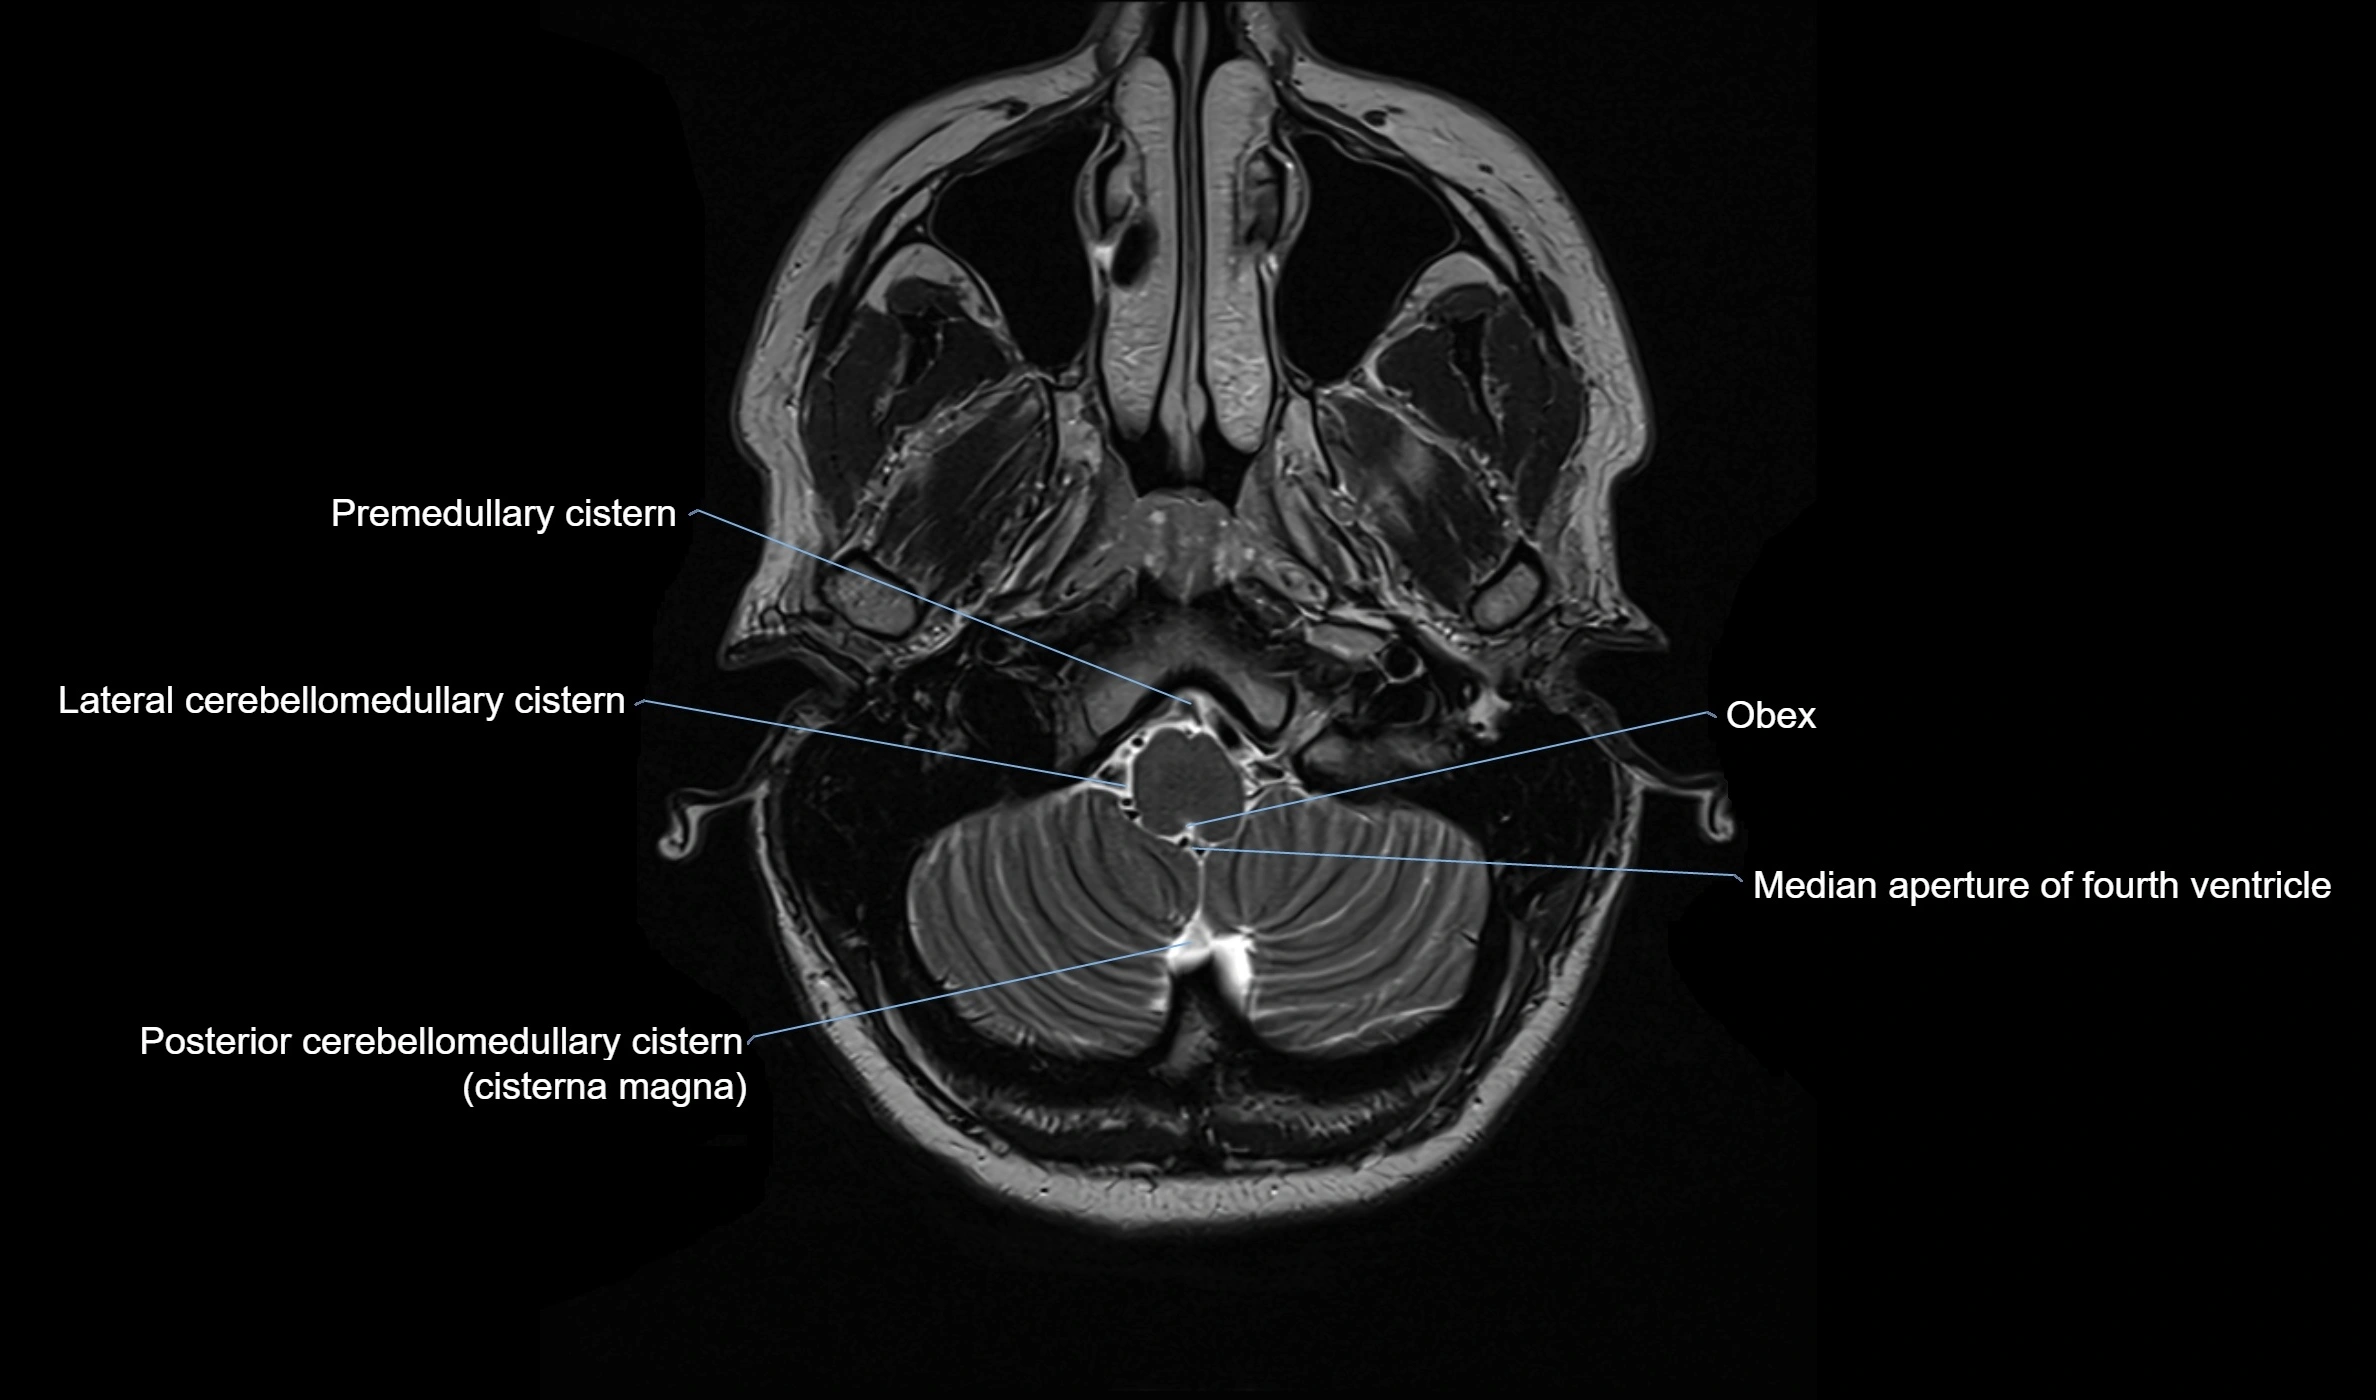

MRI images

image